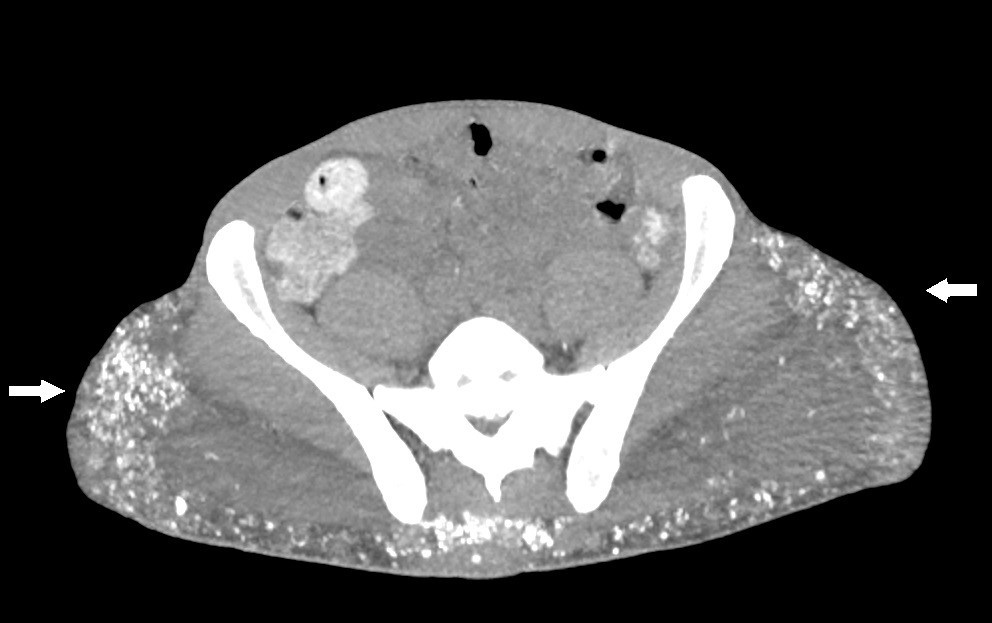

Case Presentation: A 44-year-old African American male with a medical history of human immunodeficiency virus (HIV) and chronic kidney disease (CKD) presented to the hospital with nonspecific complaints, including flank pain. Initial laboratory tests and imaging studies confirmed a diagnosis of nephrolithiasis and acute kidney injury with concomitant hypercalcemia. The patient was hospitalized and treated with intravenous fluids and pamidronate, which led to the normalization of calcium levels. Further investigation of the hypercalcemia revealed an inappropriately normal parathyroid hormone (PTH) level for the degree of calcium elevation. Additional diagnostic workup, including a computed tomography (CT) scan, revealed hyperlucent deposits in both gluteal regions. Upon questioning, the patient revealed a history of silicone injections administered 20 years earlier, raising the suspicion of exogenous overproduction of 1,25-dihydroxyvitamin D. Following treatment, his calcium levels improved, and he was advised to continue outpatient follow-up. However, one month later, he was readmitted with recurrent hypercalcemia. Due to the complexity of managing hypercalcemia in the context of CKD, the nephrology team recommended initiating denosumab, as bisphosphonates are not an appropriate medication in patients with impaired renal function. After receiving the first dose, the patient’s calcium levels improved; however, he was lost to follow-up before the second dose could be administered.

Discussion: Silicone is known to be a rare cause of hypercalcemia, often years after its administration as part of cosmetic procedures. In 1964, Winer et al. described three biopsy-proven cases of granuloma formation after silicone injection, naming them “siliconomas” [1]. They observed siliconomas with a polarized microscope, noting the presence of crystals in the tissue. This constitutes the initial evidence of silicone’s role in causing this phenomenon. The exact mechanism of this granulomatous response is not completely understood but is thought to be similar to what happens in sarcoidosis-induced granulomas [2, 3]. A recent systematic review in 2018 by Tachamo et al. described 23 cases of patients (mostly female) who had received silicone, polymethylmethacrylate, or paraffin oil, and years later developed hypercalcemia [4]. Diagnostic tools like CT scans or PET fluorodeoxyglucose (FDG) are useful in the evaluation of granulomatous diseases like sarcoidosis or amyloidosis and in the diagnostic and prognostic evaluation of malignancies [5]. Currently, there is no definitive treatment for silicone-induced hypercalcemia. Many available case reports [1, 4, 6-11] used strategies like hydration, bisphosphonates, and systemic steroids as the most common management. In our patient, due to his chronic kidney disease, bisphosphonates were not an appropriate first-line therapy, and for this reason, the managing endocrinologist considered denosumab for his outpatient therapy.